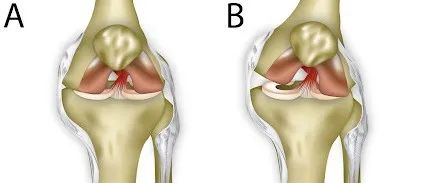

截腿踢是UFC比赛中重要的击打方式也是李小龙的必杀招之一这招必杀可以对膝关节造成破坏性的打击内侧韧带损伤,交叉韧带损伤,半月板损伤该招可以有效地破坏膝盖的韧带,从而直接KO对手我们一起来回顾一下膝关节的稳定结构典型的膝关节(胫股关节)有大约 5-10 度的过度伸展,任何更多的运动都会损伤软组织和韧带结构。对于像截腿踢这样的创伤性打击,可能会对几个结构造成伤害:韧带:有 4条重要的韧带有助于防止过度运动...

本文未经授权禁止转载肘关节脱位合并桡骨小头骨折及尺骨冠状突骨折是一种复合性损伤。包括肘关节(后)脱位,尺骨冠状突骨折,桡骨头(颈)骨折3方面,缺少一不可。因治疗效果差,而被国内学者译为「肘关节恐怖三联征」。与一般简单的肘关节脱位不同的是,“恐怖三联征”存在肘关节内在不稳定因素,因此需要手术治疗。一表理清肘关节损伤三联征治疗流程肘关节损伤三联征治疗流程图损伤机制损伤常见于高坠伤或高速运动下损伤,旋后位的轴向挤压及肘关节外翻应力致尺骨鹰嘴向后或后外侧移位,导致肘关节脱位(图1)。...